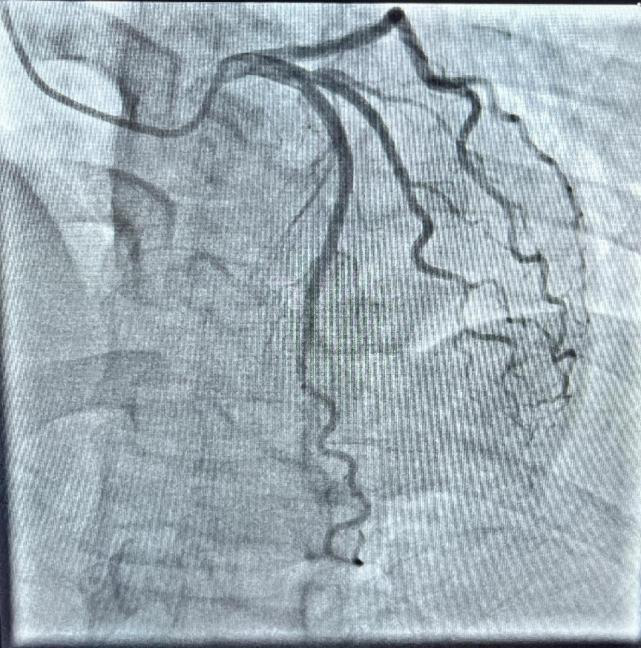

心脏冠脉造影

数字减影血管造影的原理是将注入造影剂前后拍摄的两帧X线图像经数字化输入图像计算机,通过减影、增强和再成像过程来获得清晰的纯血管影像,同时实时地显现血管影。